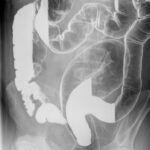

A 44 year old man with previous interstitial nephritis

Barium enema with contrast

Via email advice line from primary care: This man was diagnosed with interstitial nephritis secondary to mesalazine (prescribed for ulcerative colitis) in 2009. His eGFR has remained stable since and is currently 42. Last year he was started on lisinopril … Continue reading →

Posted in Gastrointestinal, Renal | Tagged Level B